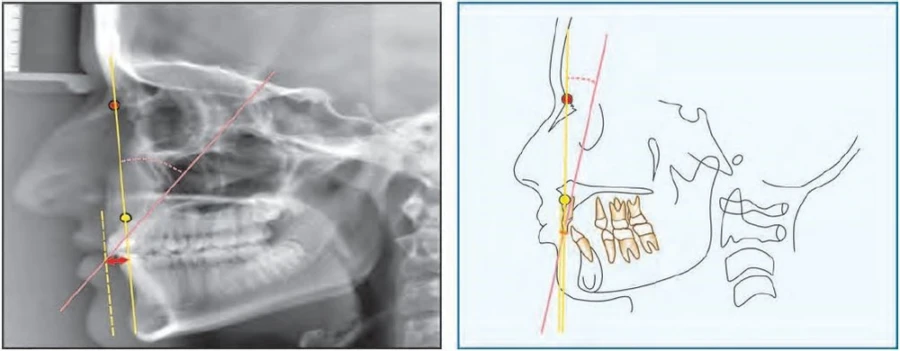

139-151. PHÂN TÍCH STEINER Cecil C. Steiner đã đi xa hơn một bước khi ông đưa ra một phân tính…